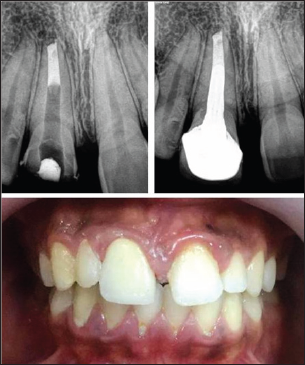

Management initiated with removal of metal-ceramic crown using a crown remover. Pain management for non-vital immature tooth was done following protocols in accordance to the previous reports through root canal therapy with apexification [4]. As a definitive restoration post endodontic treatment, a metal ceramic crown with a collarless design was given (Figure 3). After 1 year follow-up, gingival inflammation has completely resolved and presented normal form of gingival margin which is thinner and sharper (Figure 4). A periapical radiograph was exposed and it revealed, continuity in lamina dura and consistent width of periodontal ligament space, suggests healing of periapical lesion (Figure 5).

Figure 3.

Figure 4.